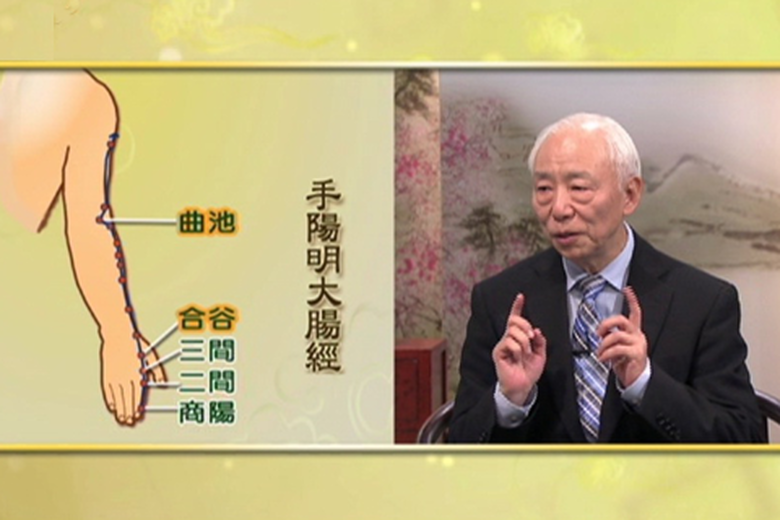

治免疫系統疾病 就按天星十二穴 |談古論今話中醫(218)

2015-12-30 11:26:15曲池善治肘中痛,合穀可治頭痛面腫。